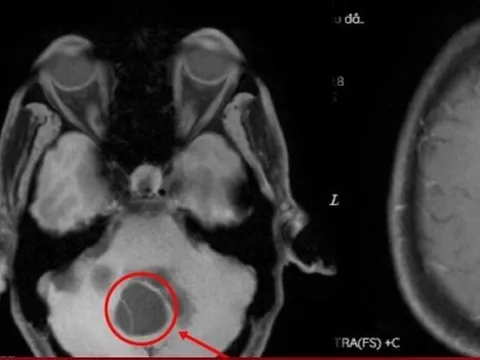

Người đàn ông phát hiện ung thư thận di căn sau khi có dấu hiệu bất thường này suốt 1 tháng

Ung thư thận thường không gây ra các triệu chứng rõ rệt cho tới khi khối u lớn hơn hoặc đã có di căn.